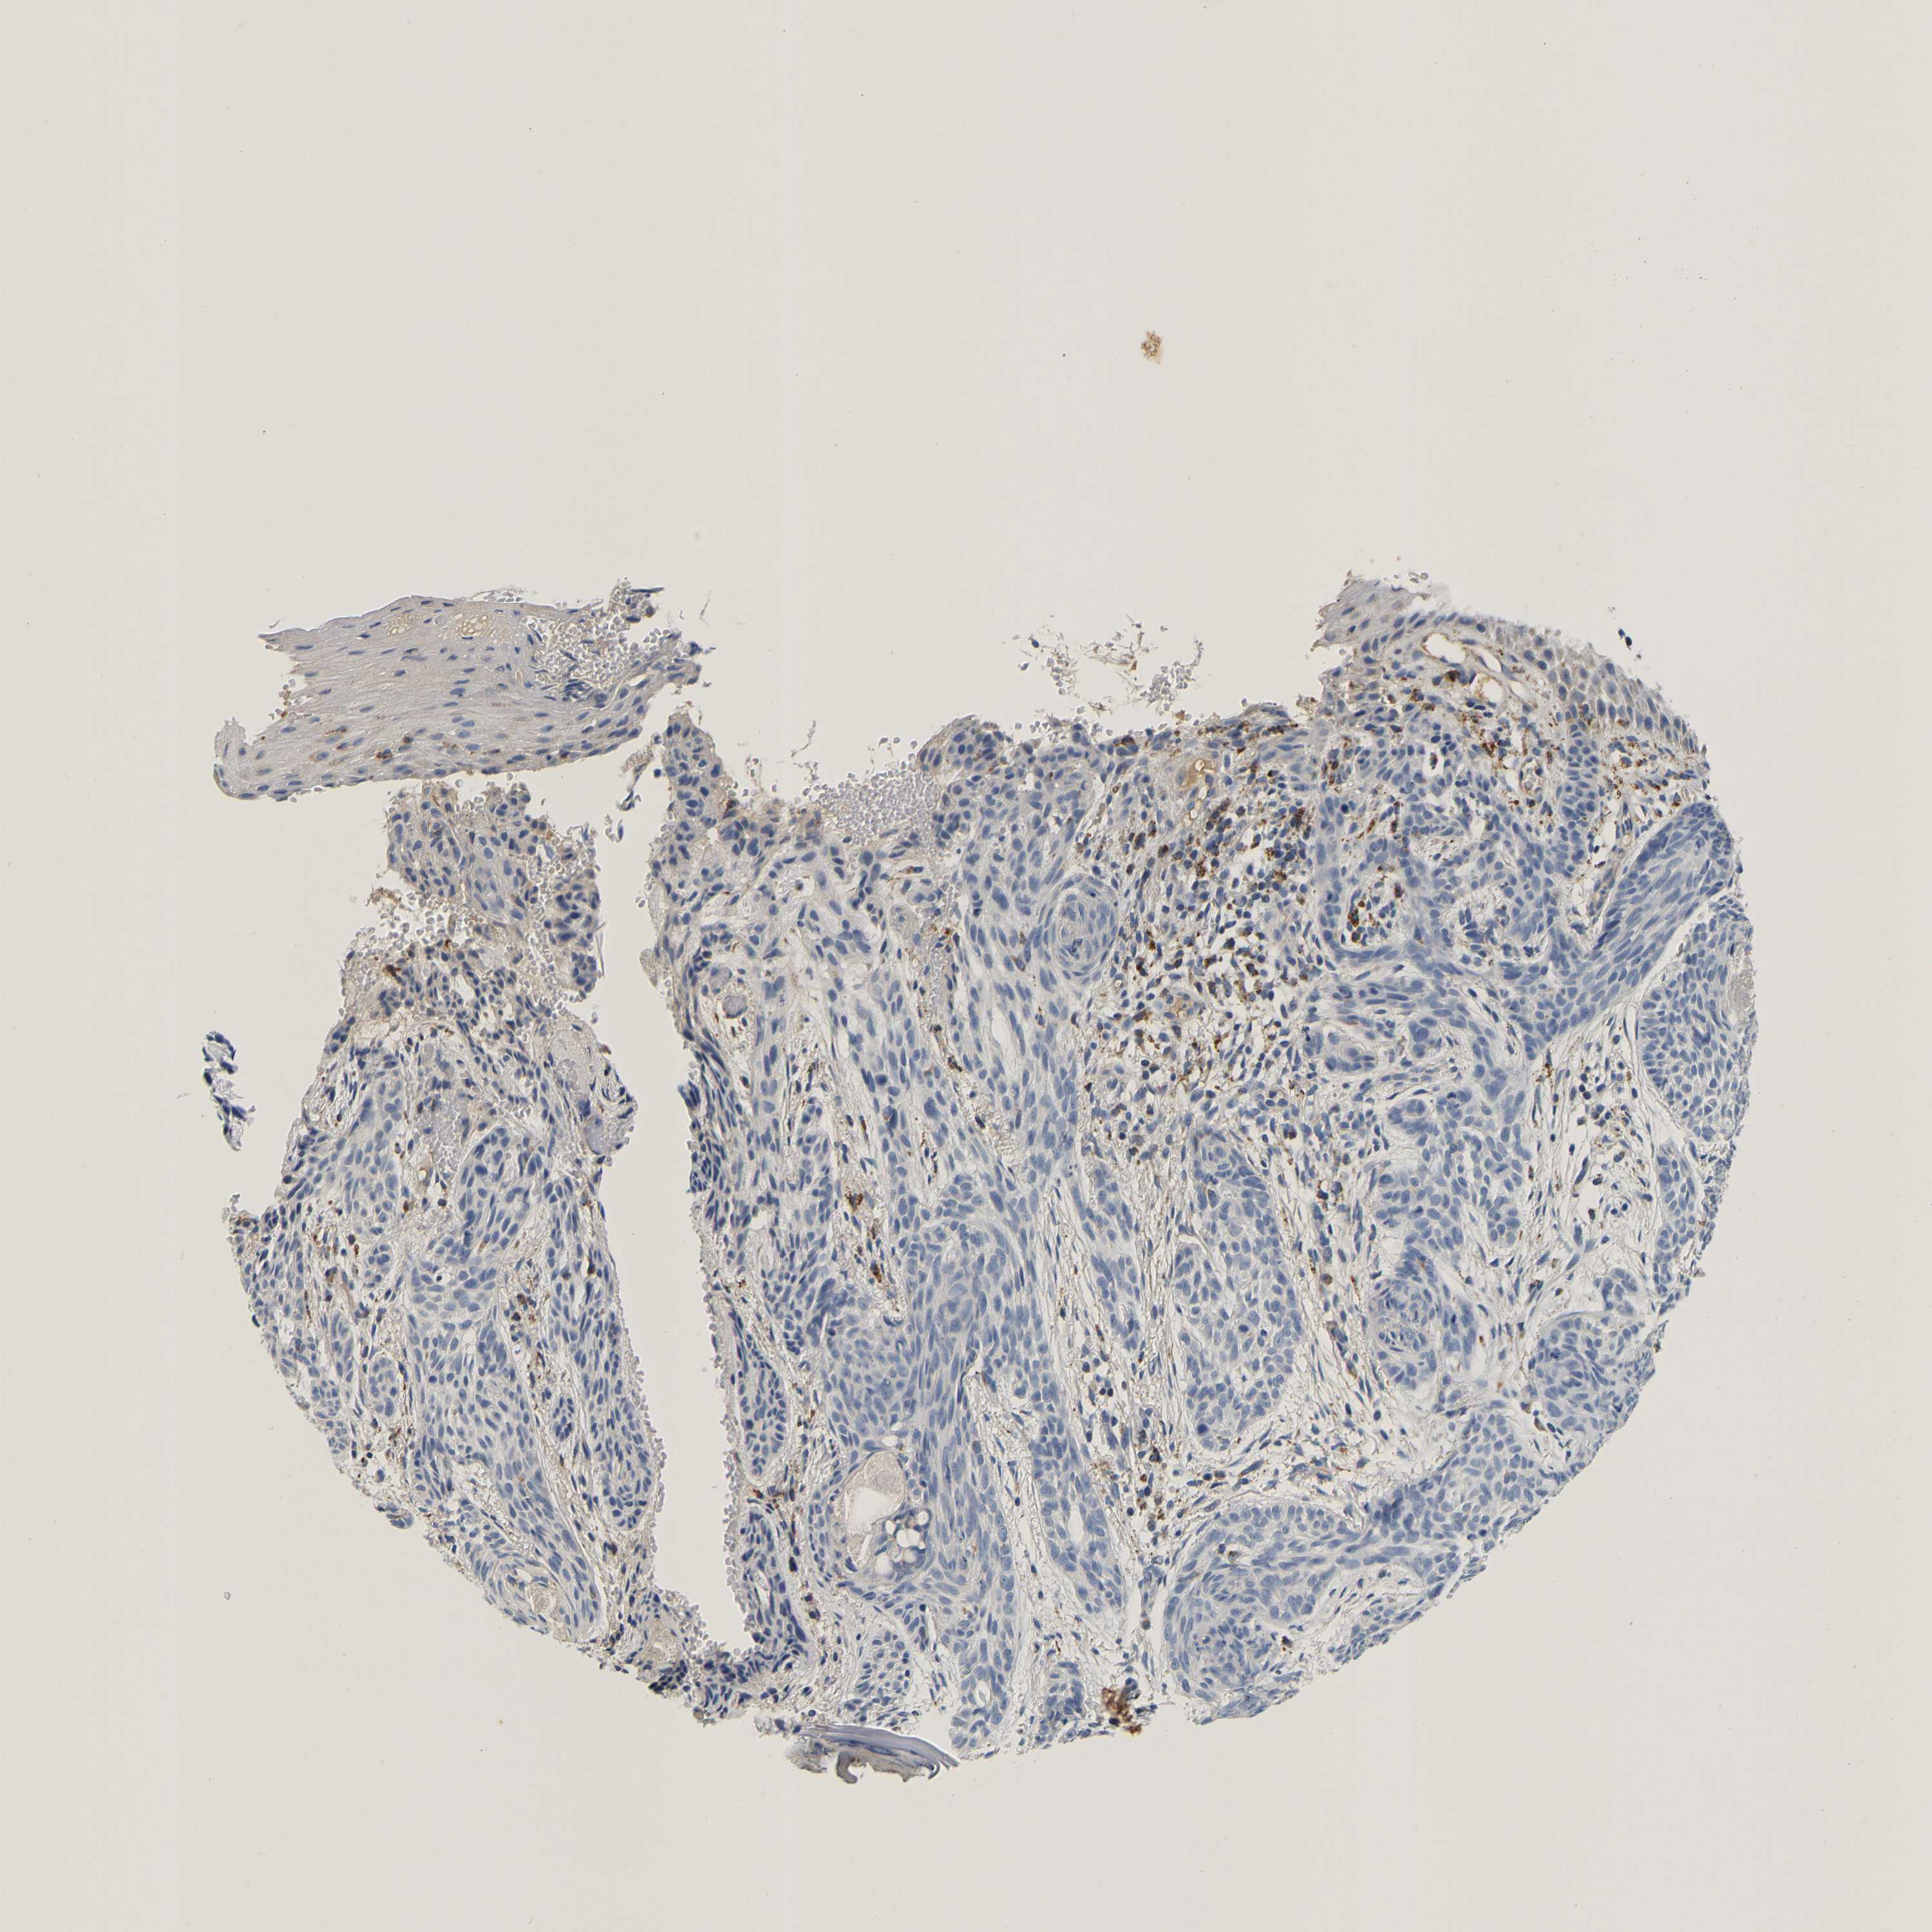

SKIN CANCER - Protein expressioni

A mouse-over function shows sample information and annotation data. Click on an image to view it in a full screen mode. Samples can be filtered based on level of antibody staining by selecting one or several of the following categories: high, medium, low and not detected. The assay and annotation is described here.

Antibody stainingi

Antibody staining in the annotated cell types in the current human tissue is reported as not detected, low, medium, or high, based on conventional immunohistochemistry profiling in selected tissues. This score is based on the combination of the staining intensity and fraction of stained cells.

Each image is clickable and will lead to virtual microscopy that enables deeper exploration of all samples and also displays staining intensity scores, fraction scores and subcellular localization as well as patient and tissue information for each sample.

Antibody HPA051162

Basal cell carcinoma

Squamous cell carcinoma, NOS

Squamous cell carcinoma, metastatic, NOS

Squamous cell carcinoma in situ, NOS